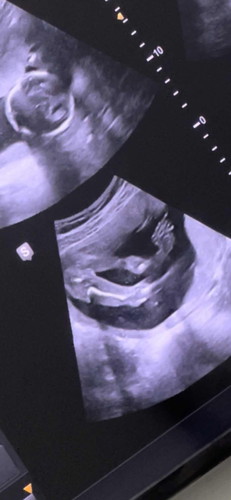

18+6 แล้วคะ หมอบอกว่าค่อนข้างไปทางเพศหญิง เพราะมองไม่เห็นอะไรเลยที่หว่างขา แล้วหมอก็บอกว่า ซาวไม่เก่ง 😒แนะนำให้เราไปซาว4 มิติ อีกคลีนิคนึง แต่ลูกเรานอนท่าตีลังกาเลยคะ ท่ายากสำหรับหมอ 😂 เพื่อนๆว่า ญ / ช คะลุ้นมาก

ผญค่ะ เห็นเหมือนกลีบ

ถ้าผช.ต้องแบบนี้ค่ะ🤣

ถ้ามีอะไรโผล่ออกมาชายแน่นอนค่ะ ไม่ต้องลุ้นเลย

น่าจะหญิงนะคะ